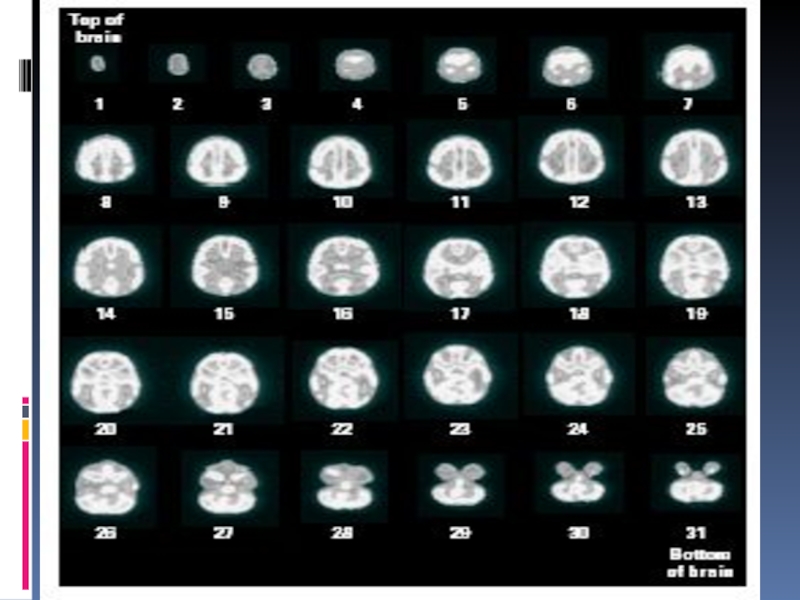

Слайд 40Позитронно-эмиссионная томография (ПЭТ)

Оценивает метаболическую активность в различных участках мозга

Испытуемый проглатывает

радиоактивное соединение (2-дезоксиглюкоза, изотоп углерода, фтора, кислорода, азота), позволяющее проследить

изменение кровотока, что косвенно указывает на уровень метаболической активности

Время полураспада изотопов от 110 сек для фтора до 120 сек для кислорода

Радиоактивные изотопы излучают позитроны, которые встречая в мозге электроны, уничтожаются, излучая гамма-лучи.

Позитронно-эмиссионная томография (ПЭТ)Оценивает метаболическую активность в различных участках мозгаИспытуемый проглатывает радиоактивное соединение (2-дезоксиглюкоза, изотоп углерода, фтора, кислорода,

Слайд 41Позитронно-эмиссионная томография

Позитронно-эмиссионная томография

Слайд 42Позитронно-эмиссионная томография (ПЭТ)

В специальной камере монтируются детекторы гамма-лучей, собранные в

кольца

В камеру помещается голова испытуемого

Полученные данные обрабатываются компьютером

ПЭТ позволяет снимать

«динамические картины» функционирования мозга, решающего ту или иную задачу или пребывающего во сне

Недостаток метода – не фиксируются быстропротекающие процессы, так как и кислород, и глюкоза попадают в мозг с током крови в течение нескольких минут

Позитронно-эмиссионная томография (ПЭТ)В специальной камере монтируются детекторы гамма-лучей, собранные в кольцаВ камеру помещается голова испытуемогоПолученные данные обрабатываются

Слайд 45PET (positron emission tomography) scan

PET (positron emission tomography) scan